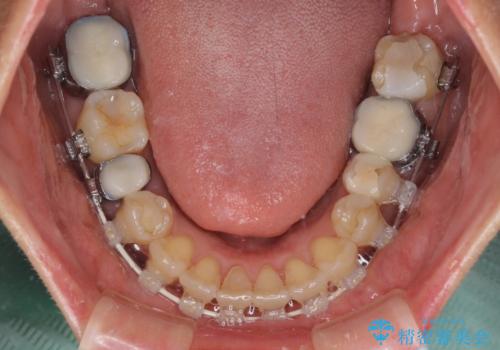

- 矯正装置

- 審美装置

- 前歯のデコボコを気にして来院された患者様です。

舌突出癖により、上下前歯がなかなか接触せずに治療期間を要しましたが、舌のトレーニングにより無事に治療を終えることができました。